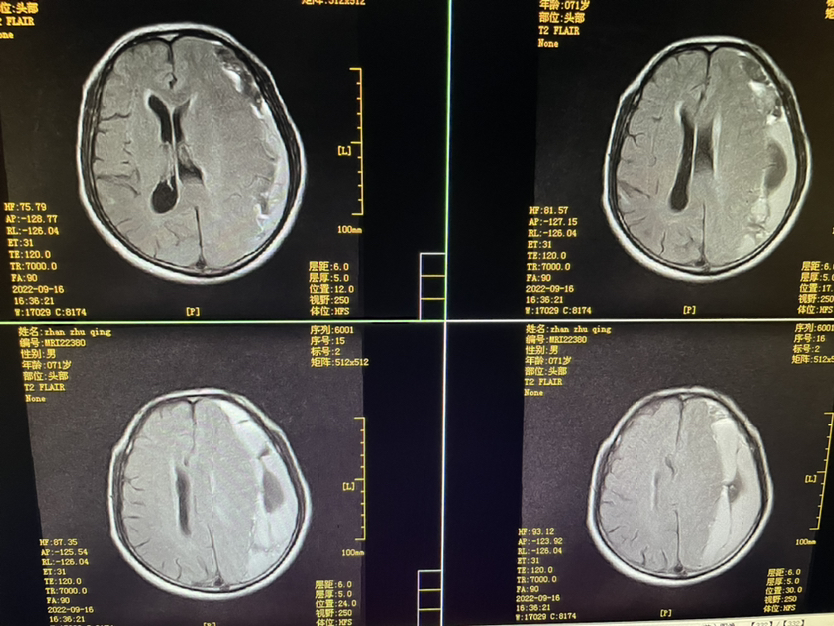

448859,头疼四肢乏力4天,71y